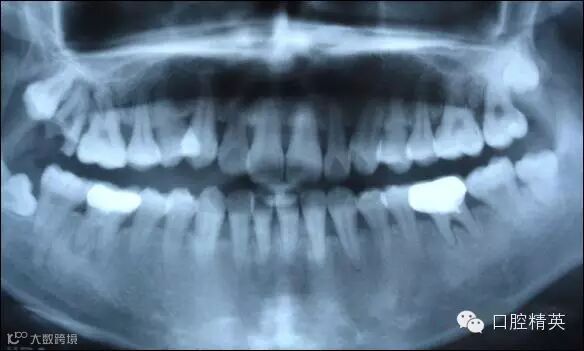

上图为健康人的全口曲面断层片,俗称全景片

从上图可以看出,牙槽骨被吸收,牙龈萎缩,牙缝变大